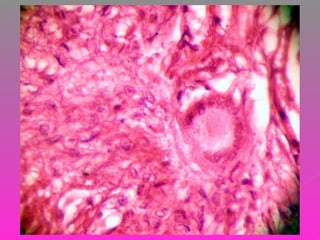

 SE RECIBE TEJIDO ÓSEO CON ABUNDANTE

MATERIAL DE ASPECTO CASEOSO,

FRIABLE CON UN VOLUMEN DE 2 CM. SE

INCLUYE LA TOTALIDAD DE LA MUESTRA

PARA SU ESTUDIO.

 TUBERCULOSIS ÓSEA ( MAL DE POTT )

 SE NOTIFICA RESULTADO AL SERVICIO DE